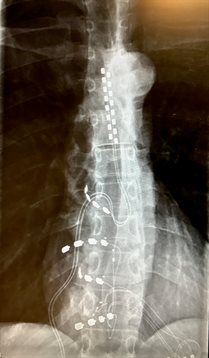

The procedure involved placing four paddle-shaped electrodes across small collections of nerves in the spinal nerve known as the dorsal root ganglion (DRG).

In a further novel development, the paddle implant was combined with a standard spinal cord stimulator to create a hybrid model.

Mrs Cameron was referred to University Hospital Southampton five years ago after a cryoblock caused a collapsed lung. She received an initial standard percutaneous stimulation implant – delivered non-surgically through the skin – along the spinal nerve but this reduced her pain by just 50%.